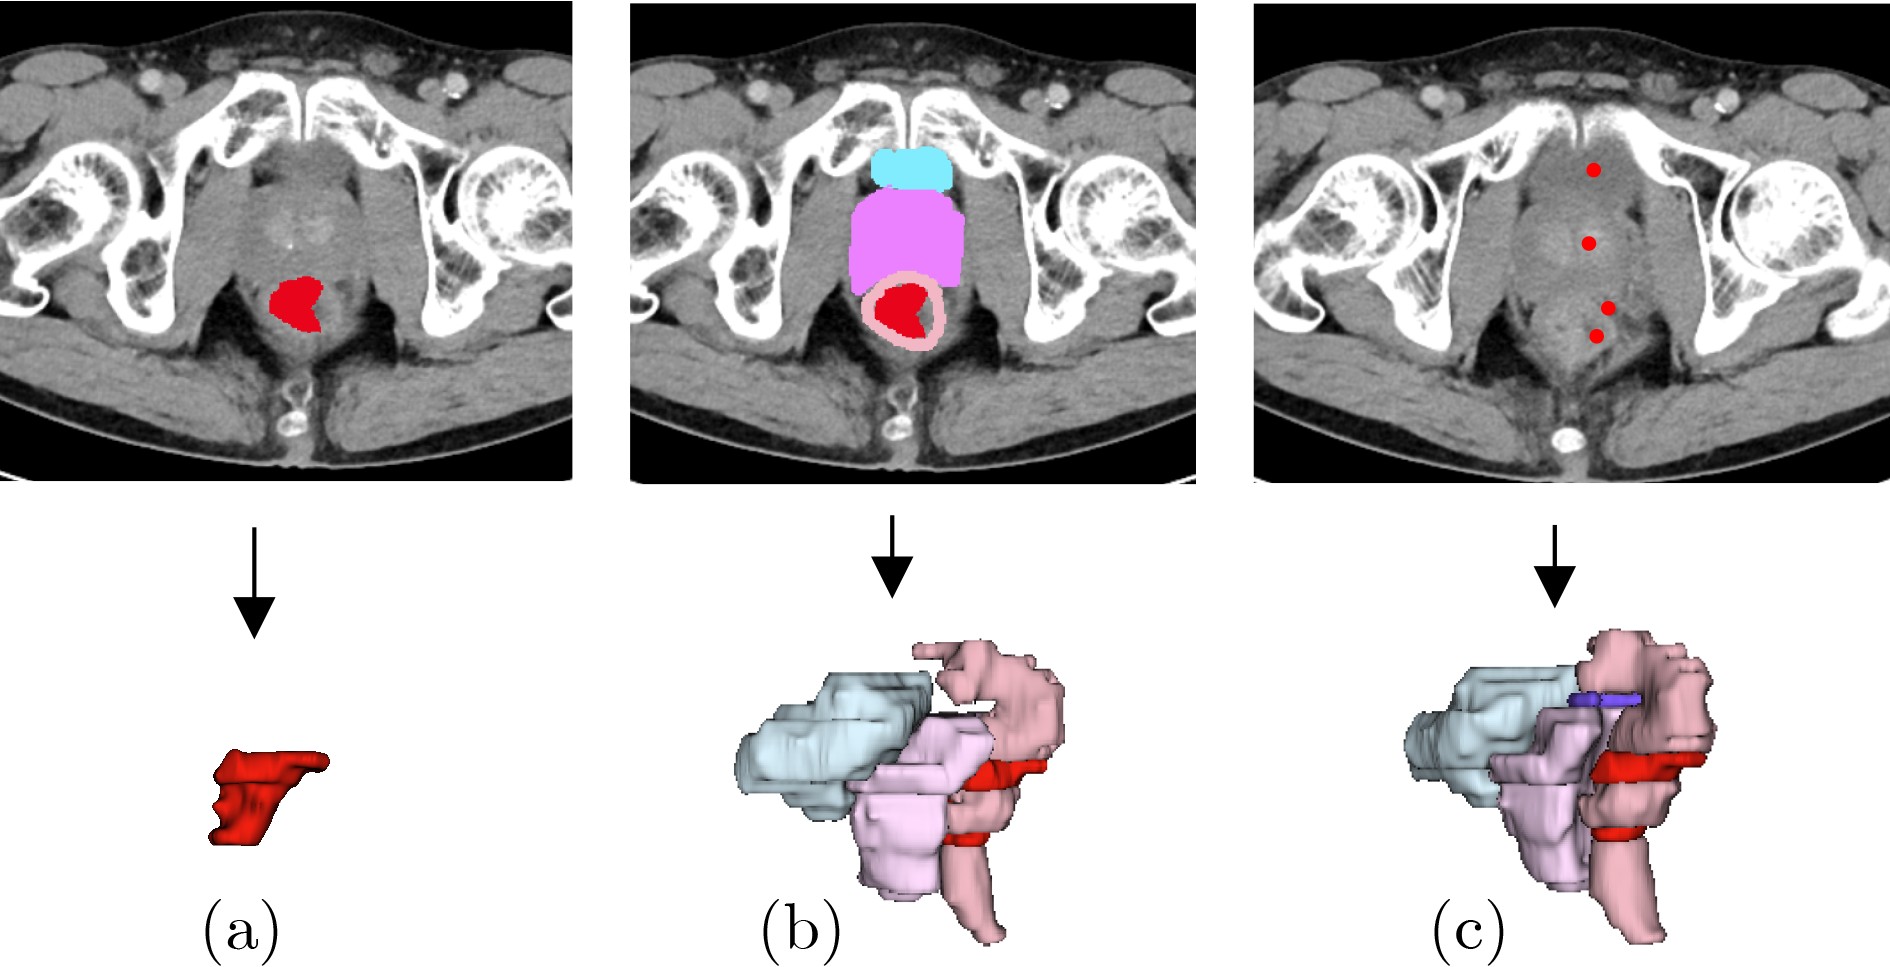

面向稀疏辐射观测的无监督三维医学图像分割方法

俞晓帆, 邹兰兰, 顾文琦, 蔡君, 康彬, 丁康

2026, 48(3): 947-959. doi: 10.11999/JEIT250841

摘要:

神经衰减场是一种具有前景的三维医学图像重建方法,此方法利用稀疏辐射测量实现与完整观察相接近的重构精度。该文提出一种无监督三维医学影像分割方法,将无监督分割与神经衰减场集成为一个端到端的网络架构。具体而言,所提网络架构包括两个阶段:稀疏测量重建和交互式三维图像分割。两个阶段可通过联合学习自适应实现互惠优化。为解决类似肛肠等复杂病灶中边界模糊和区域过度扩展的难题,所提三维分割网络的交互式三维分割阶段设计了密度引导模块,有效利用衰减系数的先验知识,调节密度感知的注意力机制,提升三维分割泛化性能。通过与南京市中医院合作构建的结直肠癌数据集以及两个公开数据集上的大量实验证明所提方法的优越性,例如与基于全辐射观测的SAM-MED3D算法相比,所提网络仅使用14%稀疏观测值,在3个数据集的平均Dice系数提升 2.0%。